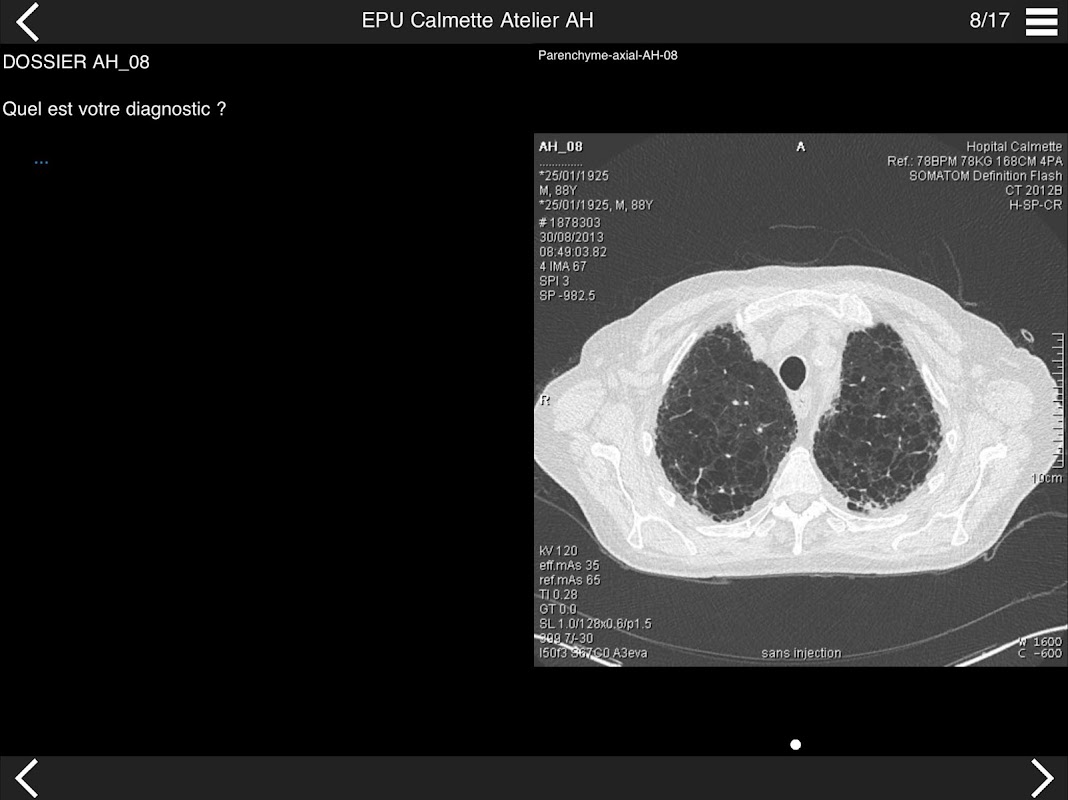

Retrouvez les cas cliniques du Cours intensif de TDM multicoupe du thorax dans cette application.

Thèmes du cours 2017 :

* BPCO et nodules pulmonaires : recommandations en 2017

* Pathologie interstitielle : lésions élémentaires et « patterns »

* Pathologie vasculaire et médiastinale

* Oncologie thoracique : bilan standard et introduction à l’étude de l’angiogénèse